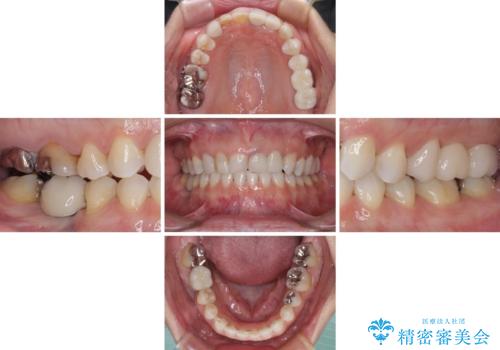

診察したところ、上顎前歯に過剰歯があることで上顎歯列が大きくなり、上下の歯が奥歯の一部でしか咬み合っていない状態でした。

咬み合わせ改善のため、前歯の過剰歯を抜去し、ワイヤー矯正にて歯列と咬み合わせることとしました。

左上の奥歯のブリッジや前歯のセラミッククラウンはいったん除去し、矯正治療後に補綴治療を行うこととしました。

上下非接触の咬み合わせは、舌突出癖によるところが大きく、トレーニングを行いながら治療を進めていきました。